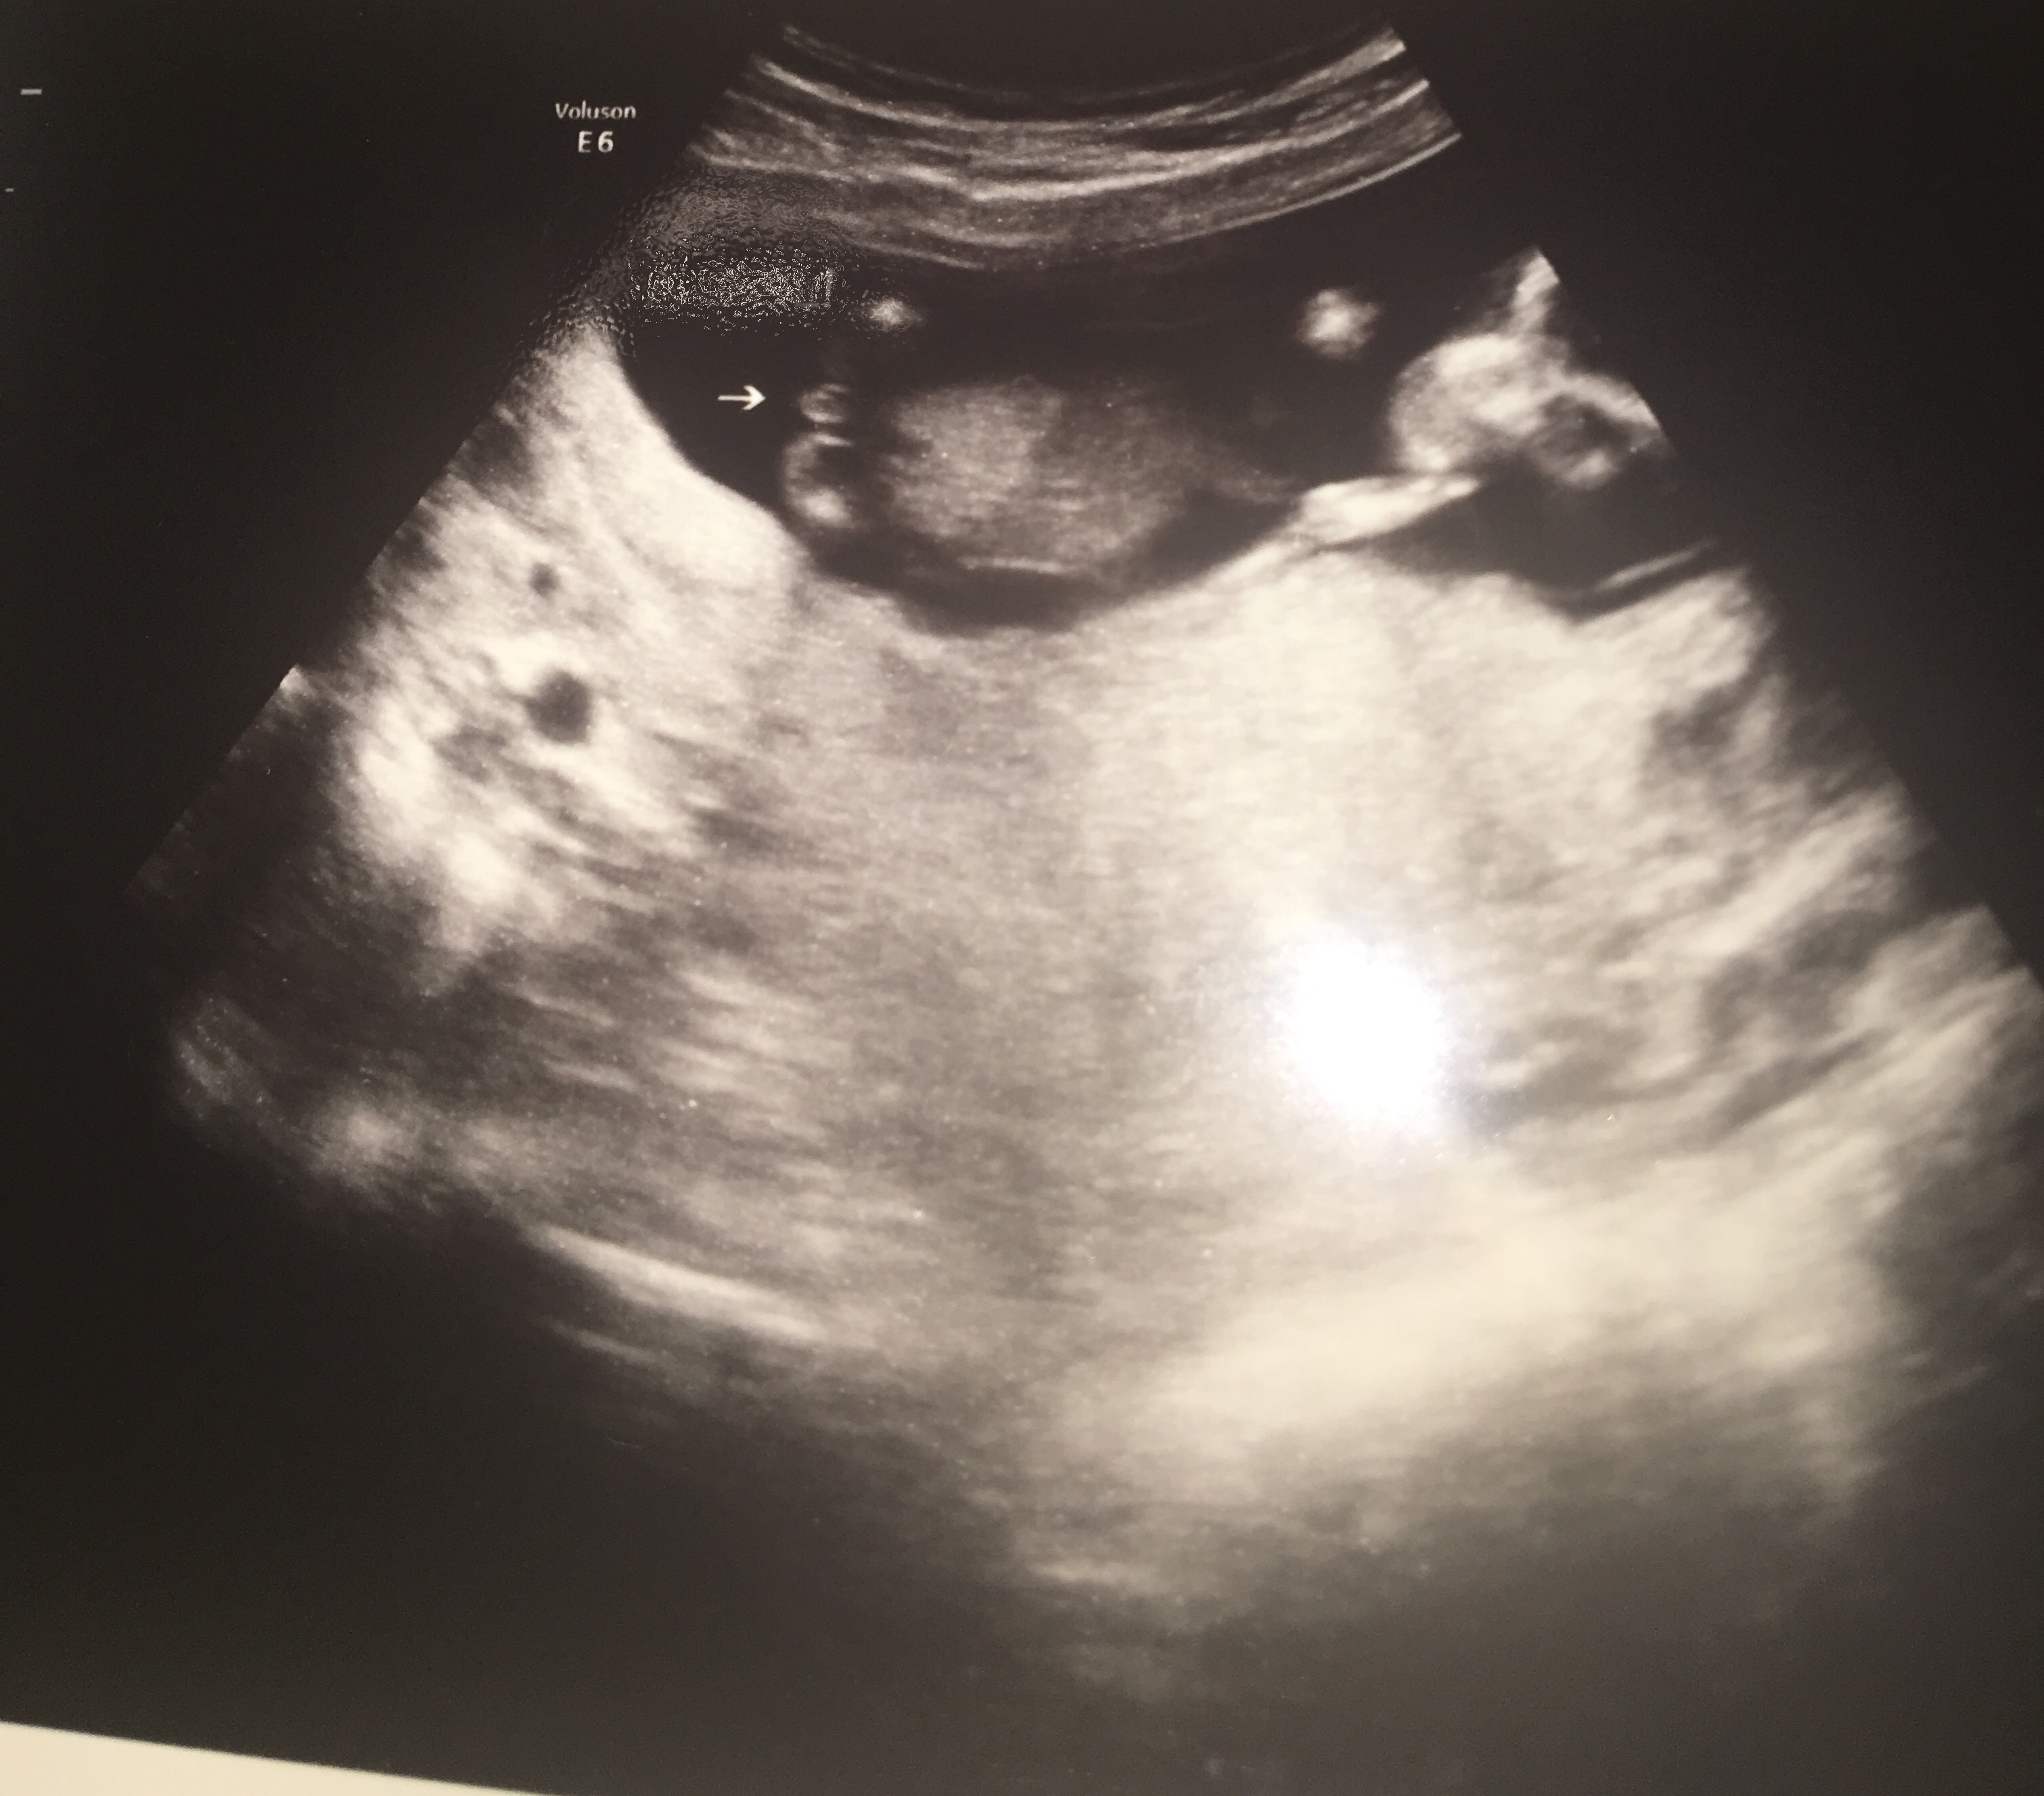

I had an elective gender scan at 15 weeks and the tech said that she was FOR SURE on the gender but

I just am not sure when I look at 2 of the 3 potty shots she gave me. I want it to be what she claims it is but I am just feeling a little unsure. Please give your input, it will be very very appreciated!! Attachment 36811Attachment 36812Attachment 36813